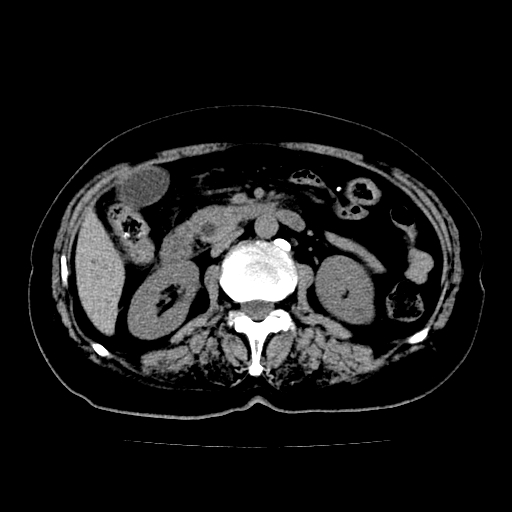

以下是引用lujiandong在2009-2-8 9:37:00的发言:[br]从所发的ct平扫图象上看,胆总管明显增粗,从上向下逐渐变细,是否有泥沙样结石,建议薄层重建;胰腺形态基本正常,左侧肾前筋膜轻度增厚。可以考虑:轻度单纯性胰腺炎,建议ct增强扫描。